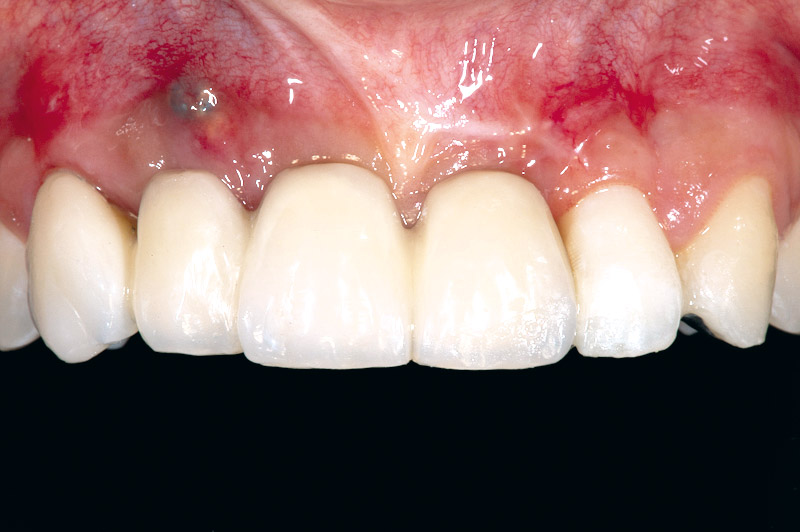

01/17 - Initial situation before surgery. Patient lost central incisors 1 month ago due to endodontic failures